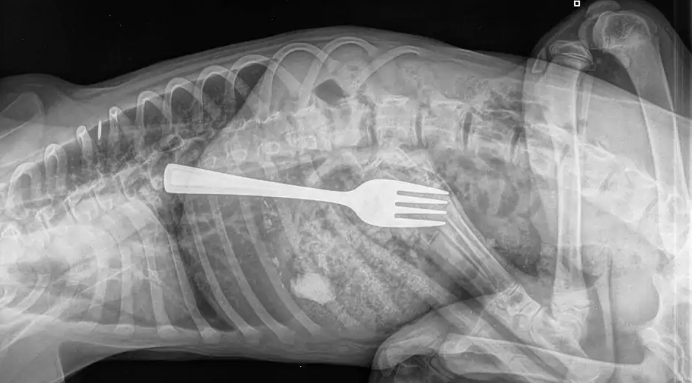

An X-ray confirmed Dustin had swallowed a fork and the medics had two options – removing it via surgery or removing it using an endoscope. Fortunately, in the case of Dustin, the latter one was a success.